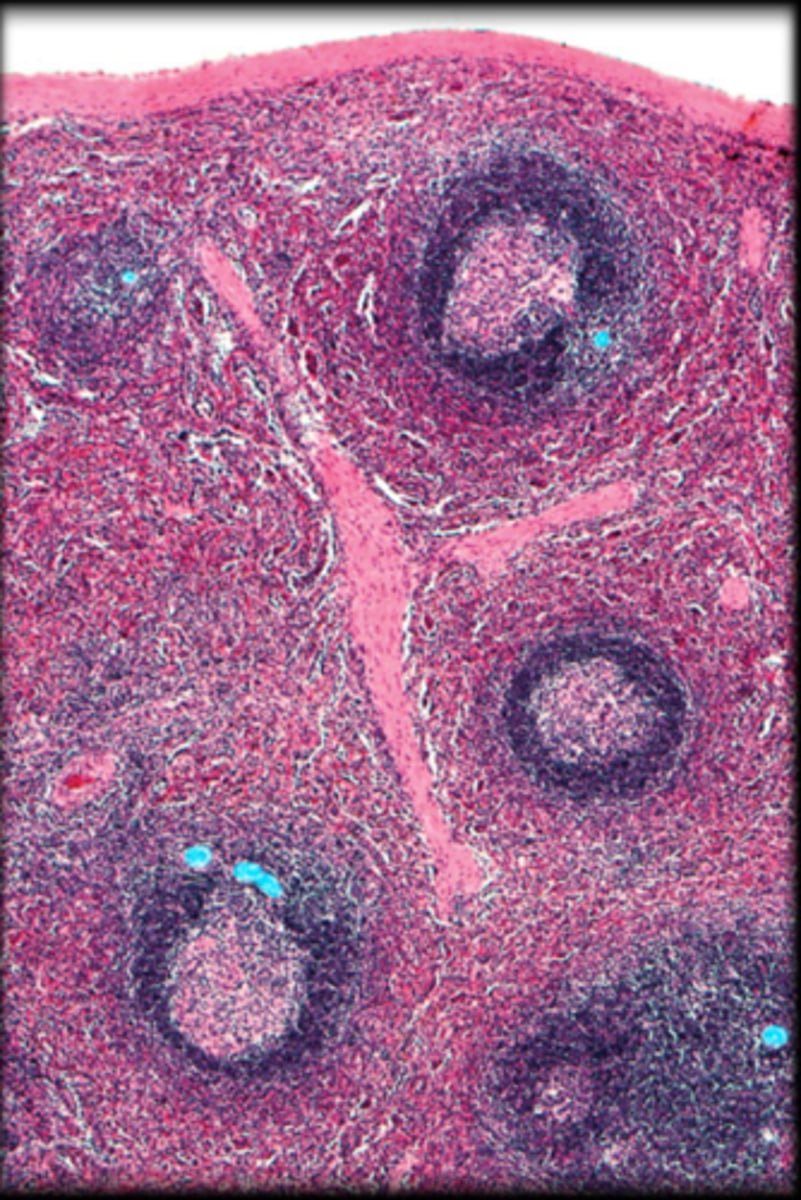

thymus

cortex

Fetal thymus

medulla

hassall's corpuscle